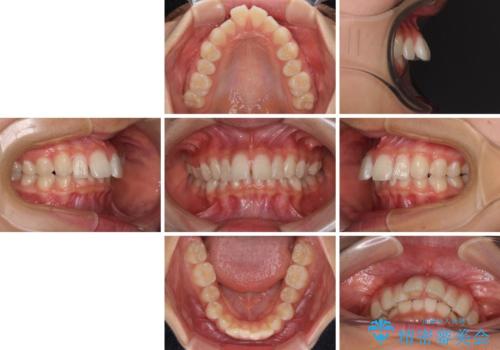

深い咬み合わせで前方に煽られた前歯 高校生のインビザライン矯正治療

- 前歯の隙間と前方に飛び出していることを気にして来院された患者様です。

奥歯の咬み合わせを見ると、上顎が下顎に対して相対的に前方にありました。

咬み合わせも深くなっていたため、上顎臼歯を後方に移動させつつ、下顎の小臼歯を直立させ、奥歯の咬み合わせを改善する必要があります。

奥歯の咬み合わせと深い咬み合わせを改善した後、隙間などをインビザラインで整えることとしました。